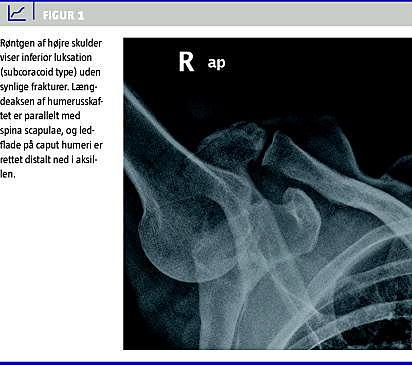

Patienten mødte i skadestuen med fuldt abduceret og let udadroteret højre arm. Ved klinisk undersøgelse kunne man palpere caput humeri i aksillen, og der var svære smerter, hvis man forsøgte at adducere armen. Der var normal sensibilitet i nervus axillaris' område lateralt på skulderen (regiment badge area ), dog var der let snurrende fornemmelse i spidsen af fingrene, som forsvandt efter reponering. Røntgenundersøgelse af højre skulder viste inferior luksation (subcoracoid) uden synlige frakturer (Figur 1 ).

Røntgenundersøgelse er sædvanligvis tilstrækkeligt til at bekræfte diagnosen [3]. På røntgen ses længdeaksen af humerusskaftet parallelt med spina scapulae, og ledfladen på caput humeri er rettet distalt ned i aksillen (Figur 1).